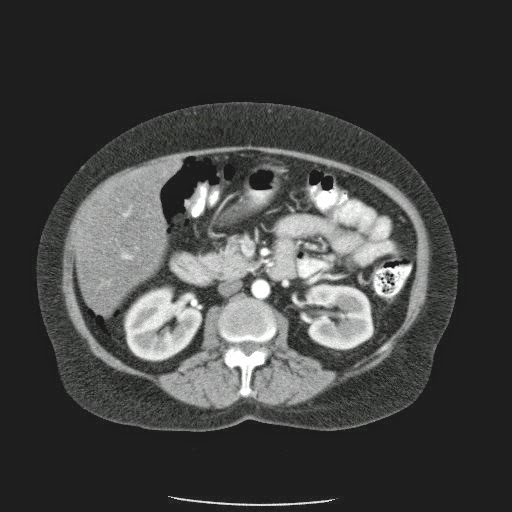

Caso Interesante #4

Adulto masculino, 1 semana de fiebre y malestar general.

¿Dónde esta ubicado el hallazgo?